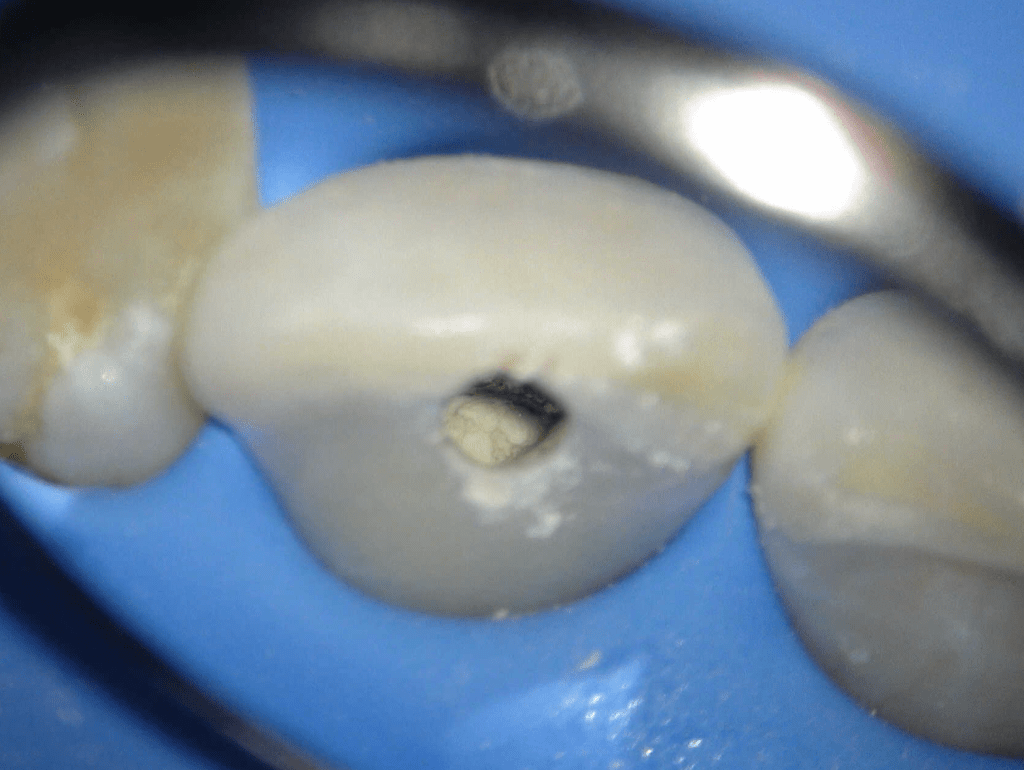

Reconstrucción preendodóntica

Molar superior

Reco palatina

Reco pared vesticular

Reco pre-endo gingivectomái, pared yuxtaosea

Reco pre-endo, molar inferior

Reco preendo + 4 conductos molar superior

Reco preendo + gingivectomía

Reco preendo, 2o Molar superior

Reconstrucción debajo de puente